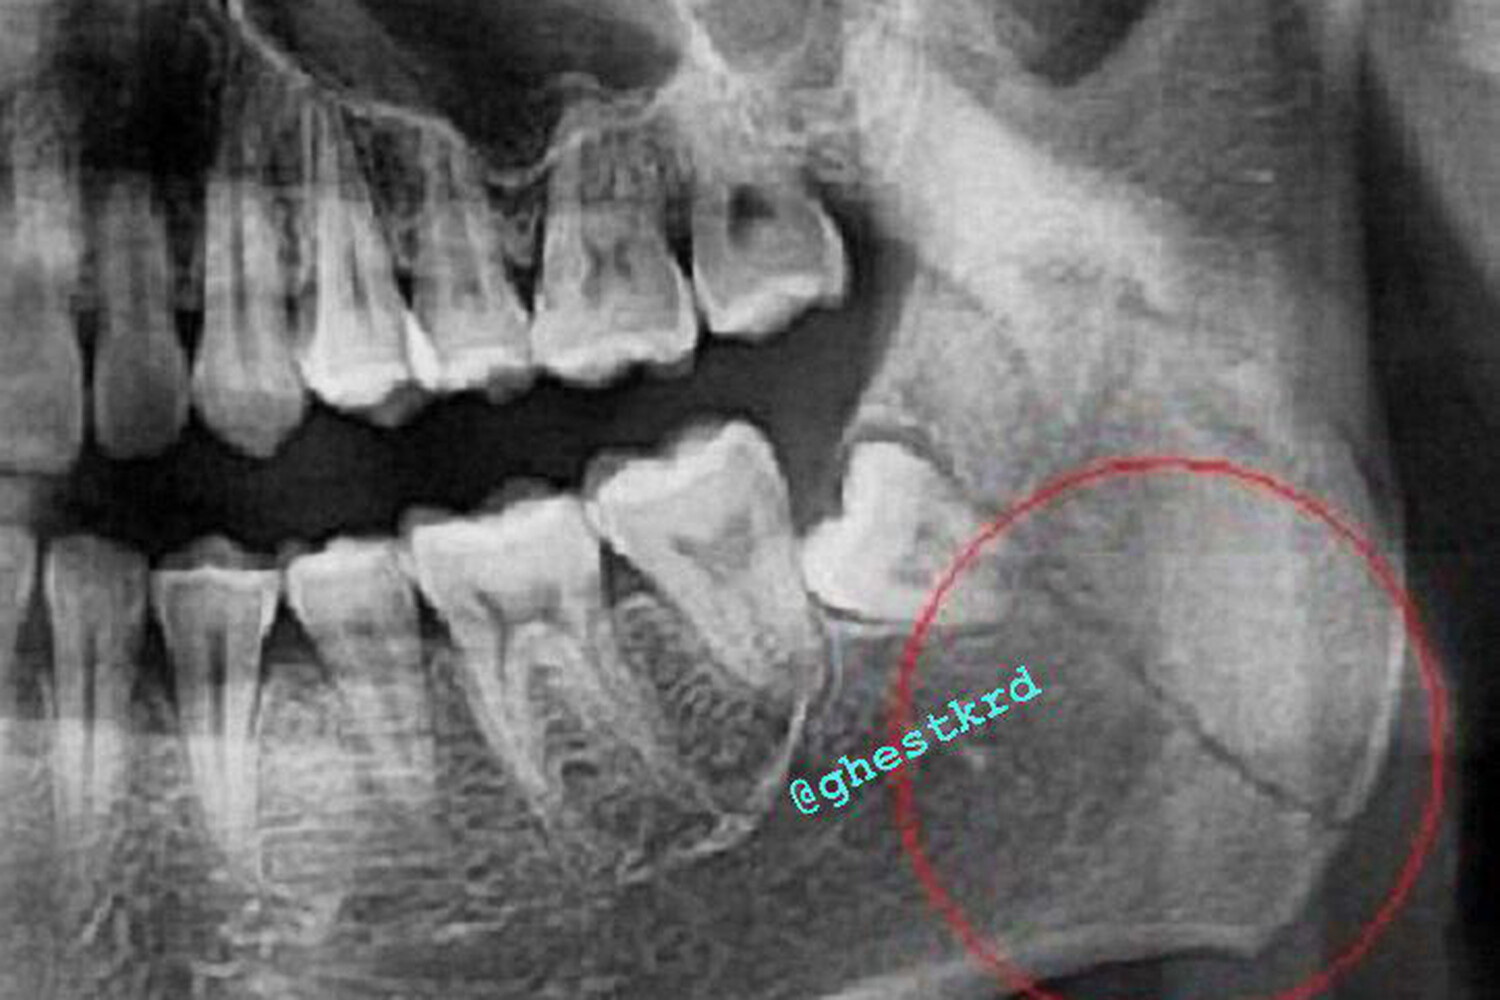

В результате происшествия пострадавший получил серьезную травму — перелом нижней челюсти, потребовавший госпитализации. После обращения потерпевшего в правоохранительные органы начались оперативно-розыскные мероприятия.